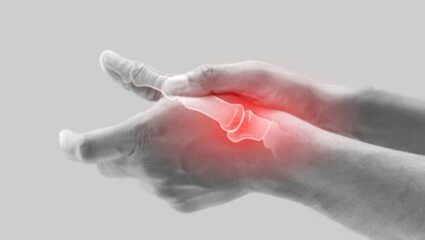

Home Remedy : थंडीत हाडे आणि सांध्यांमधील वेदना दुपटीने जाणवू लागतात. याचे मूळ कारण म्हणजे शरीरात वाढणारे युरिक अ‍ॅसिड. काही पदार्थांना आहारातून निष्कासित करून तुम्ही शरीरातील युरिक अ‍ॅसिडचे प्रमाण कमी…

सांध्यांमध्ये जमा झालेले युरिक ॲसिड कमी करण्यासाठी आहारात वेगवेगळ्या भाज्यांचे सेवन करावे. भाज्यांच्या सेवनामुळे शरीरातील विषारी घटक सहज बाहेर पडून जातील. जाणून घ्या सविस्तर.

सकाळी उठल्यानंतर बऱ्याचदा सांध्यांमध्ये वेदना वाढणे, कंबर दुखी, पाठदुखी, हाडांमध्ये वाढलेल्या वेदना इत्यादी अनेक समस्या उद्भवू लागतात. शरीरात युरिक अ‍ॅसिडची पातळी वाढल्यानंतर हाडांमध्ये वेदना वाढू लागतात. संधिवाताची समस्या उद्भवल्यानंतर संपूर्ण…

रक्तात वाढलेली युरिक ॲसिडची पातळी नियंत्रणात ठेवण्यासाठी आहारात वेगवेगळ्या भाज्यांचे सेवन करावे. भाज्यांच्या सेवनामुळे शरीराला अनेक फायदे होतात. जाणून घ्या सविस्तर.

हिवाळा जवळ आला की सांधेदुखी वाढते. थंडीच्या काळात युरिक अ‍ॅसिडच्या रुग्णांनी विशेष काळजी घ्यावी. शिवाय, या ऋतूत काही भाज्या खाल्ल्याने युरिक अ‍ॅसिडची समस्या वाढू शकते, जाणून घ्या अधिक माहिती

सांध्यांमध्ये वाढलेल्या वेदना कमी करण्यासाठी आणि गाउटपासून सुटका मिळवण्यासाठी आहारात या भाज्यांचे अजिबात सेवन करू नये. या भाज्यांच्या सेवनामुळे रक्तात प्युरीनची पातळी वाढते आणि शरीराला हानी पोहचते.

सांध्यांमध्ये साचून राहिलेले युरिक ऍसिड नष्ट करण्यासाठी आहारात वेगवेगळ्या भाज्या आणि फळांचे सेवन करावे. यामुळे शरीराला सुद्धा अनेक फायदे होतात. जाणून घ्या नियमित कोणत्या भाज्या खाव्यात.

चुकीच्या आहारामुळे शरीरात युरिक अ‍ॅसिड जमा होत, जे वेळीच बाहेर पडलं नाही तर शरीरात खडे तयार होण्याची शक्यता असते. काही घरगुती पदार्थांचे सेवन हे युरिक अ‍ॅसिड शरीराबाहेर काढण्यास मदत होते,…

धावपळीच्या जीवनशैलीमुळे प्रत्येक व्यक्ती कोणत्या ना कोणत्या आरोग्यासंबंधित समस्यांनी त्रस्त आहेत. त्यातील अनेकांमध्ये दिसून येणारी समस्या म्हणजे शरीरात वाढलेले उच्च यूरिक अ‍ॅसिड. कोलेस्ट्रॉल, मधुमेह आणि उच्च यूरिक अ‍ॅसिड वाढल्यानंतर शरीरात…

युरिक अ‍ॅसिडचे क्रिस्टल्स सांध्यामध्ये जमा होतात ज्यामुळे समस्यांना तोंड द्यावे लागते. जर तुम्हाला युरिक अ‍ॅसिडचे प्रमाण जास्त असेल तर या डाळी खाणे टाळा. जास्त प्युरिन असलेल्या या डाळींचे सेवन करणे…

मागील काही काळापासून अनेकांना युरिक अ‍ॅसिडची समस्या फार सतावत आहे. हे समस्या वेळीच नियंत्रणात केली नाही तर यामुळे आरोग्याच्या अनेक समस्या निर्माण होऊ शकतात. यामुळे गाउट, मूत्रपिंडात खडे आणि सांध्यांमध्ये…

आहारात होणाऱ्या छोट्या मोठ्या बदलांमुळे शरीरात युरिक अ‍ॅसिड वाढू लागते. शरीरात वाढलेली युरिक अ‍ॅसिडची पातळी आरोग्यासाठी अतिशय घातक ठरते. यामुळे सांध्यांमध्ये वेदना वाढणे, गाऊट किंवा हाडांना सूज येण्याची जास्त शक्यता…

शरीरात वाढलेले युरिक ॲसिड नियंत्रणात ठेवण्यासाठी आहारात हिरव्या चटणीचे सेवन करावे. या चटणीच्या सेवनामुळे युरिक ॲसिडची पातळी कमी होते आणि आरोग्य सुधारण्यास मदत होते. जाणून घ्या हिरवी चटणी खाण्याचे फायदे.

शरीरात वाढलेल्या युरिक अ‍ॅसिडमुळे संधिवात, हाडांमध्ये गाऊट जमा होणे, बोटांमध्ये वेदना वाढणे इत्यादी अनेक समस्या उद्भवू लागतात. रोजच्या आहारात प्युरीन युक्त पदार्थांचे जास्त सेवन केल्यामुळे सांध्यांमध्ये किंवा शरीराच्या हाडांमध्ये युरिक…

शरीरात वाढलेल्या युरिक अ‍ॅसिडमुळे सांध्यांमध्ये वेदना वाढणे, हातापायांना मुंग्या येणे इत्यादी अनेक समस्या उद्भवू लागतात. या समस्यांपासून आराम मिळवण्यासाठी आहारात या पदार्थांचे नियमित सेवन करावे.

शरीरात यूरिक अ‍ॅसिडची पातळी वाढल्यानंतर सांध्यांमध्ये वेदना होणे, संधिवात किंवा आरोग्यासंबंधित इतरही समस्या उद्भवू लागतात. यूरिक अ‍ॅसिडची पातळी वाढल्यानंतर शरीरात ही गंभीर लक्षणे दिसून येतात.

युरिक अ‍ॅसिडची समस्या झपाट्याने वाढत आहे. याचे सेवन अनेक समस्यांना आमंत्रण देत असते. अशात काही पदार्थांचे सेवन करून तुम्ही शरीरात वाढलेले युरिक अ‍ॅसिड नियंत्रणात करू शकता.

जर तुम्हालाही घाणेरड्या युरिक अ‍ॅसिडचा त्रास होत असेल, तर येथे जाणून घ्या की युरिक अ‍ॅसिड कमी करण्यासाठी आहारात कोणत्या गोष्टींचा समावेश करता येईल. हे पदार्थ शरीराला आतून स्वच्छ करतात.

शरीरात युरिक अ‍ॅसिडची पातळी वाढल्यानंतर सांध्यांमध्ये क्रिस्टल जमा होऊ लागतात.यामुळे गुडघे दुखू, सांध्यांना आलेली सूज किंवा वेदना वाढण्याची शक्यता असते.या वेदना कमी करण्यासाठी नियमित आलं आणि ओव्याचे पाण्याचे सेवन करावे.